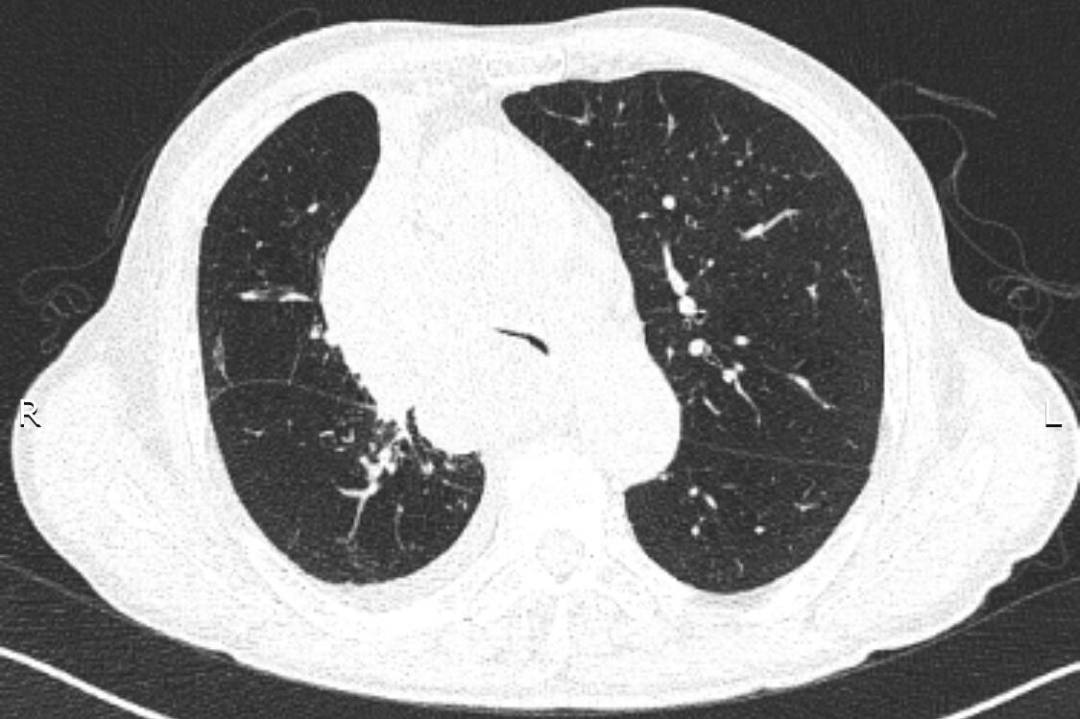

入院后給予吸氧、藥物治療,癥狀緩解不明顯。張強(qiáng)主任結(jié)合患者的癥狀、體征及CT表現(xiàn),考慮憋喘主要為腫瘤浸潤壓迫氣道引起,緊急行電子氣管鏡檢查,明確了氣道被壓迫情況。正常成人氣管內(nèi)鏡約2.5cm,患者氣管下段重度狹窄,直徑僅約3mm,而且狹窄一直延續(xù)到右主支氣管末端,左主支氣管狹窄情況還稍輕些。建議患者可緊急置入支氣管支架短期緩解癥狀,綜合支架特點、支架定制周期、患者病情、費(fèi)用等情況后,家屬希望能為患者盡快放置硅酮支架。張強(qiáng)主任立即聯(lián)系醫(yī)務(wù)科,并聯(lián)系支架置入經(jīng)驗豐富的外請專家王曉東教授前來指導(dǎo),為患者保駕護(hù)航。

支架放置前:CT提示近圓形的氣管被壓迫至“一條縫”